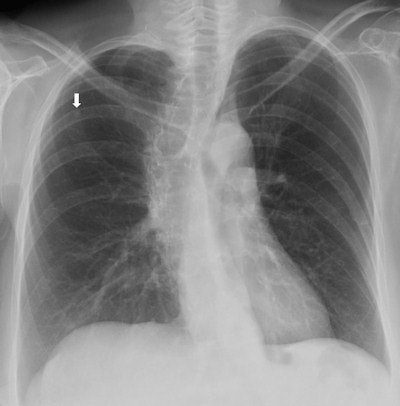

Top: Follow-up imaging of a 72-year-old woman. Preoperative x-ray for skin melanoma. Posteroanterior chest radiography in the upright position shows one suspected pulmonary nodule in the right lung (arrow). Bottom: Digital tomosynthesis image clarifies that the same opacity corresponds to a focal sclerosis within the poster arch of a right rib (arrow). Readers provided a confidence score of 1.Tomography findings were proven by CT (114 patients), chest x-ray during follow-up (105), or histology (18). The final diagnoses included 77 pulmonary opacities, 26 pulmonary scars, 12 pleural lesions, and 122 pulmonary pseudolesions. Tomosynthesis versus chest x-ray presented a higher (p < 0.05) sensitivity (92% vs 15%), specificity (91% vs 9%), overall accuracy (92% vs 12%), and diagnostic confidence (area under ROC, 0.997 vs 0.619). Mean effective dose of chest x-ray vs tomosynthesis was 0.06 vs 0.107 mSv (p < 0.05).